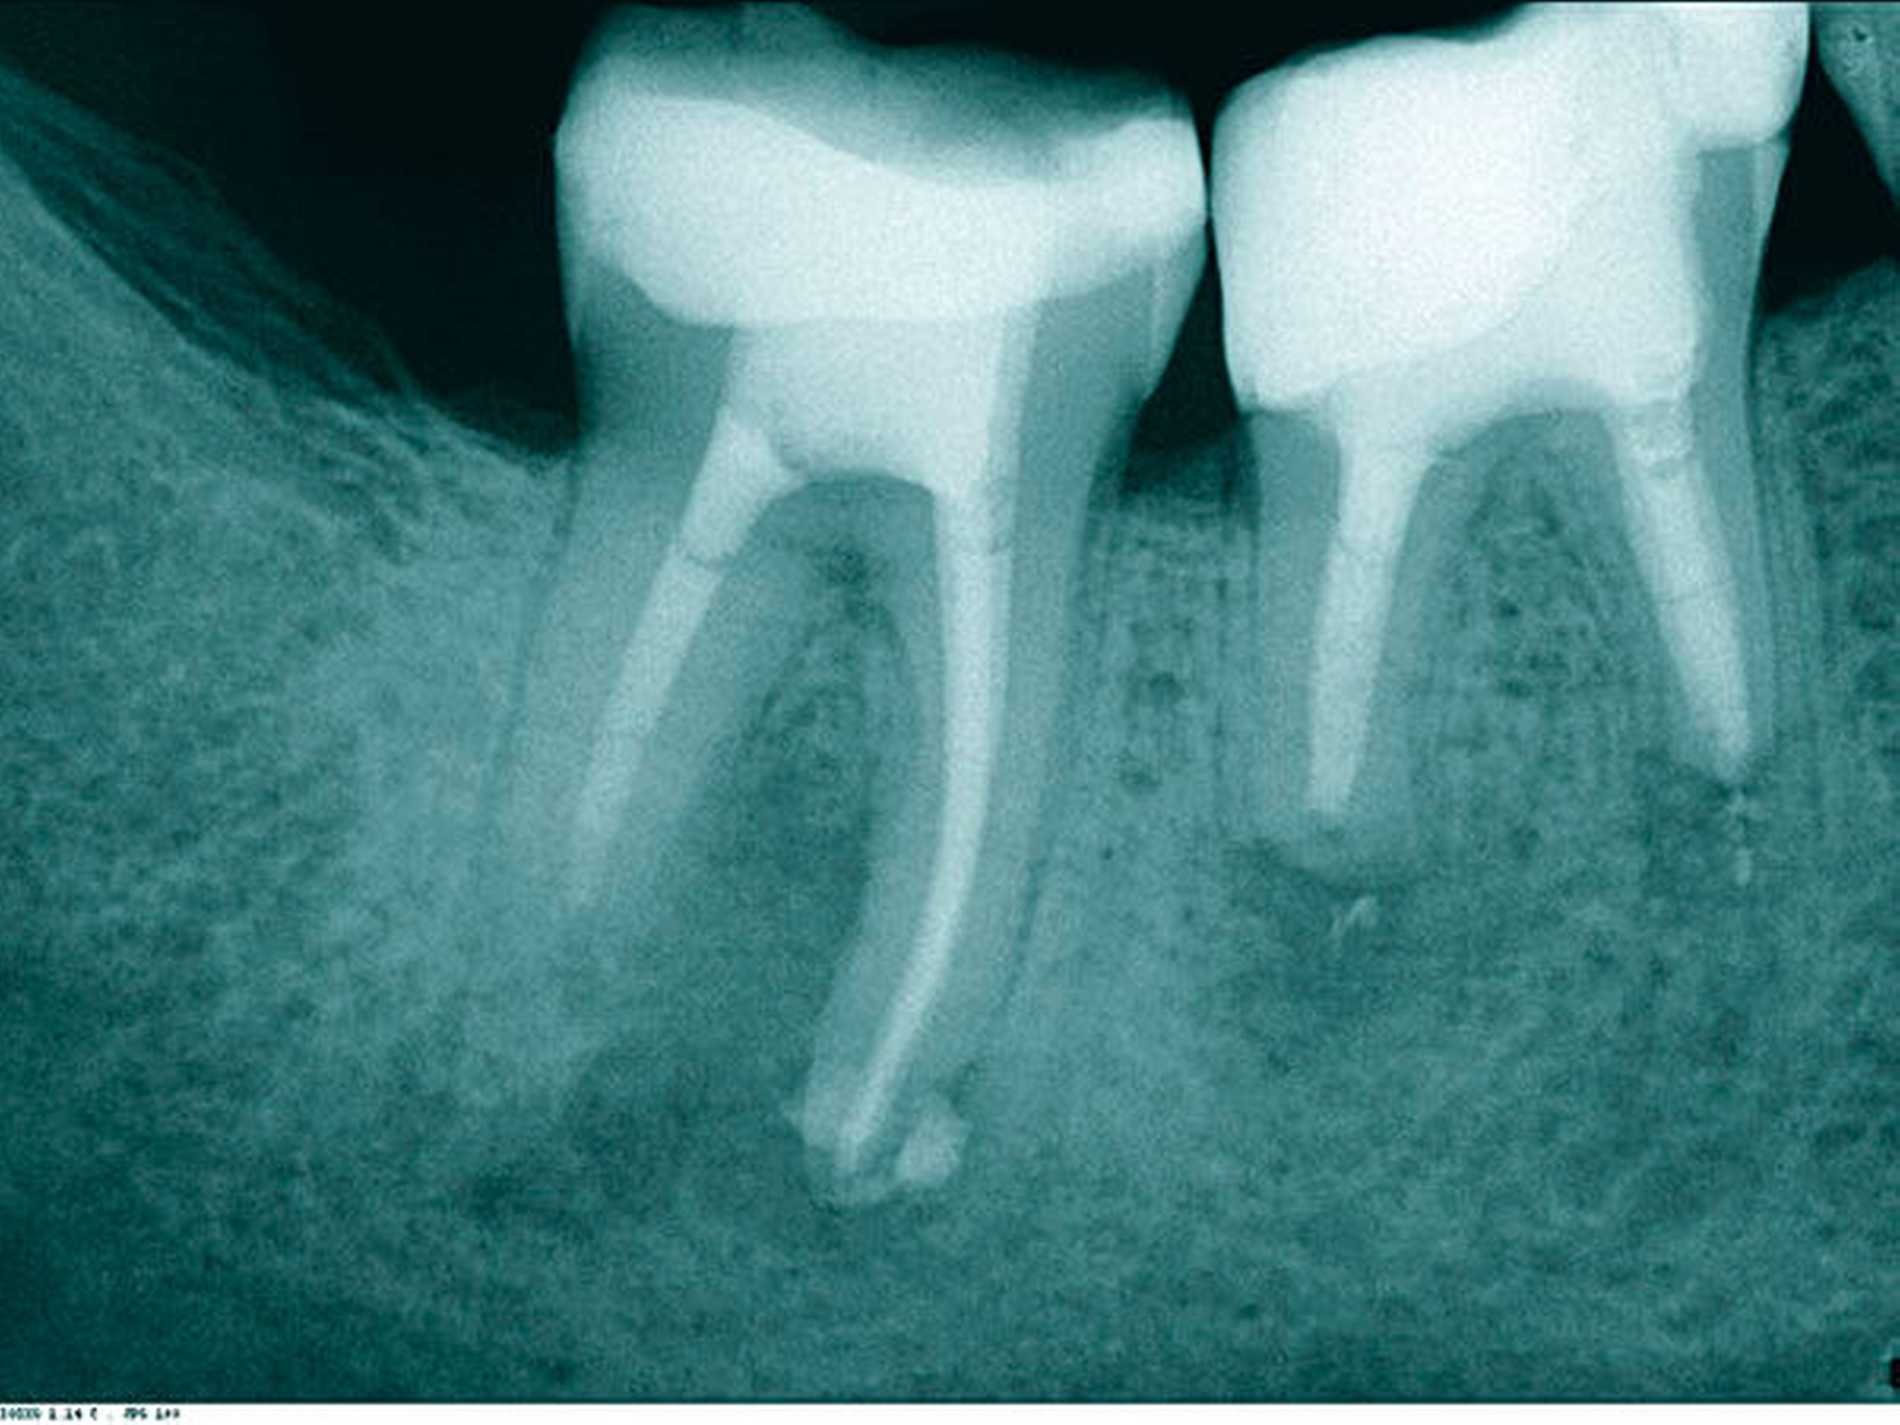

In der ersten Therapiesitzung erfolgte – nach Isolierung mit Kofferdam – die Trepanation des Zahnes und die Stiftentfernung mit Ultraschallinstrumenten. Im Anschluss wurden die drei gefüllten Kanäle revidiert, der vierte, nicht abgefüllte, mesiobukkale Kanal dargestellt und präpariert. Die elektronische Längenmessung ergab 14,5 mm für den mesiobukkalen Kanal, 17,0 mm für den mesiolingualen, 15 mm für den distobukkalen und 16 mm für den distolingualen. Aufgrund der großen initialen Kanaldurchmesser und der guten Einsicht bis ins periapikale Gewebe (Abbildung 2) wurde auf eine Längenmessaufnahme verzichtet. Die Desinfektion erfolgte mit Natriumhypochlorid (NaOCl) 5 Prozent und EDTA 17 Prozent, sowie Schallaktivierung mittels EDDY-Spitzen (VDW, München). Das Wurzelkanalsystems wurde manuell mit K-Feilen bis IS0 70 präpariert. Es folgte eine medikamentöse Einlage mit AH Temp (DentsplySirona, Bensheim). Danach wurde eine Aufnahme zur Kontrolle der vollständigen Guttapercha-Entfernung und der suffizienten Einbringtiefe des Kalziumhydroxids angefertigt (Abbildung 3).